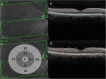

Background: Tissue derived biomarkers may offer utility as indicators of accumulated damage. Reduced thickness of retinal neuronal tissue and the vascular choroid have previously been associated with vascular damage and diabetes. We evaluated associations between retinal thickness, retinal microvascular and choroidal measures, and renal function in a population with a high burden of comorbidity.

Methods: Participants were recruited from nuclear cardiology or renal medicine clinics. Retinal and choroidal thickness were measured from spectral-domain optical coherence tomograms. Retinal microvascular parameters were assessed from digital fundus photographs using a semi-automated software package.

Results: Participants (n = 241) had a mean age of 65 years and a mean eGFR of 66.9 ml/min/1.73m2. Thirty-nine % of the cohort had diabetes and 27% were using diuretics. Thinning of the inner retina and changes to its microvascular blood supply were associated with lower eGFR and CKD stages 4 and 5, while no associations were found between the outer retinal layers or their choroidal blood supply and CKD of any stage. These associations remained following adjustment for age, mean arterial blood pressure, diabetes status, low-density lipoprotein, body mass index, and sex.